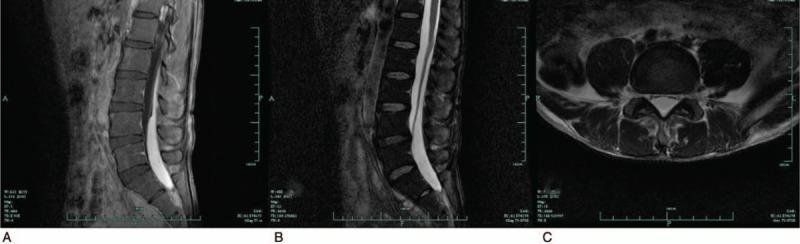

A magnetic resonance imaging (MRI) scan on the third day after the onset of symptoms revealed a subdural hematoma from L1 to S1, presenting as hyperintensities on T1 weighted sequences and hypointensities to isointensities on T2 weighted sequences.

症状发作后第三天进行的磁共振成像(MRI)扫描显示,L1至S1水平存在硬膜下血肿,在T1加权序列上表现为高信号,在T2加权序列上表现为低信号至高信号。